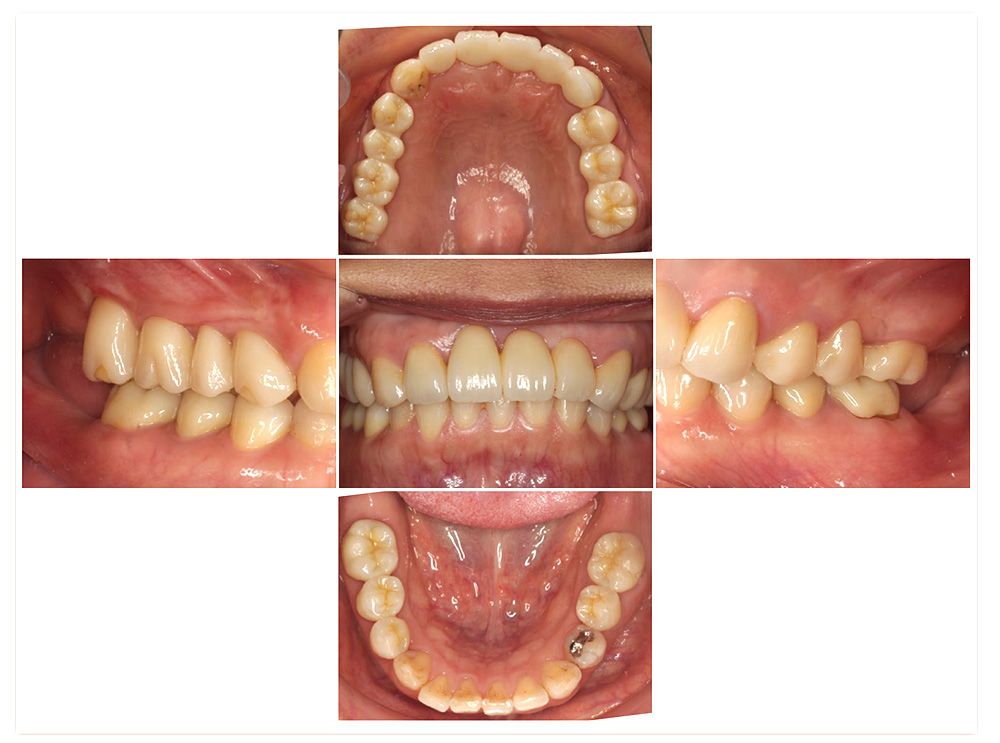

症例紹介